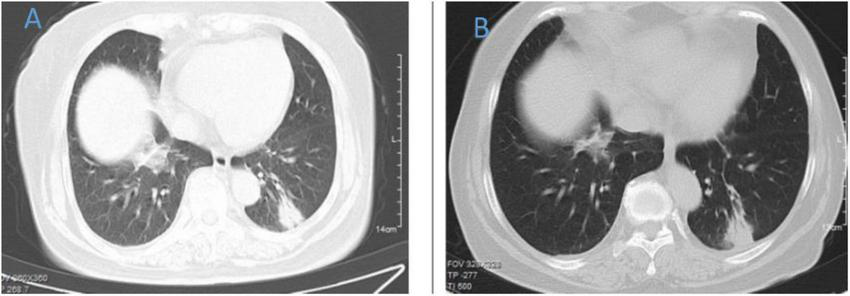

FIGURE 1

Chest CT of patient 1. (A) Before treatment on September 7, 2022; (B) the follow-up imaging 1 week after treatment showed progression compared to the pre-treatment scans.